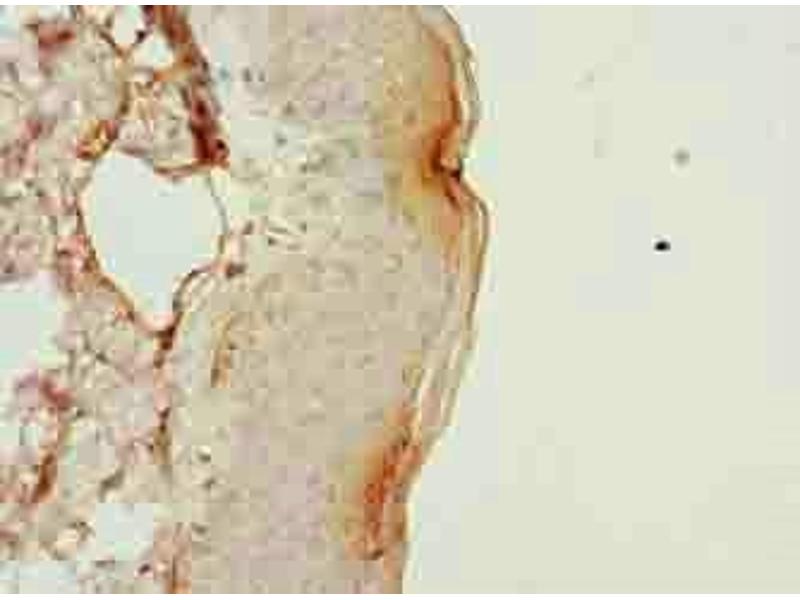

PLGRKT anticorps (AA 1-147)

Aperçu rapide pour PLGRKT anticorps (AA 1-147) (ABIN7163544)